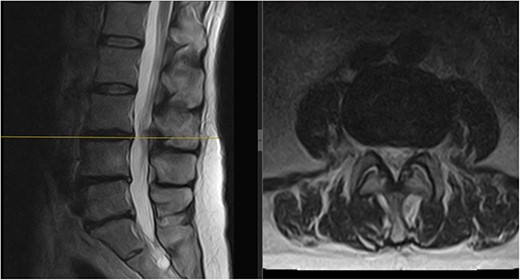

A 64-year-old female secretary presented with severe LBP and left anterior thigh pain that began 6 weeks prior to presentation whilst cleaning her house. She had no loss of bowel or bladder control, saddle anaesthesia, unintentional weight loss, or loss of appetite. A physical exam revealed decreased forward flexion, intact sensation, and intact motor function of the lower extremities. There was some tenderness in the left hip and gluteal regions. The straight leg raise was negative on the left but the femoral stretch test was mildly positive. Initial imaging showed an L3/L4 central and left paracentral disc extrusion with compression of the left L4 transiting nerve roots (Fig. 1). Benign haemangiomas were present at L2 and L4, along with a benign perineural cyst at S2. The patient was reassured and shown how to perform the motor control exercise programme as modified by the senior author (https://youtu.be/xJiAqVsfpRc) (Fig. 2).

Initial MRI scan of the lumbar spine: initial MRI scan of the lumbar spine performed in July 2022 showing the left-sided L3/4 disc prolapse.